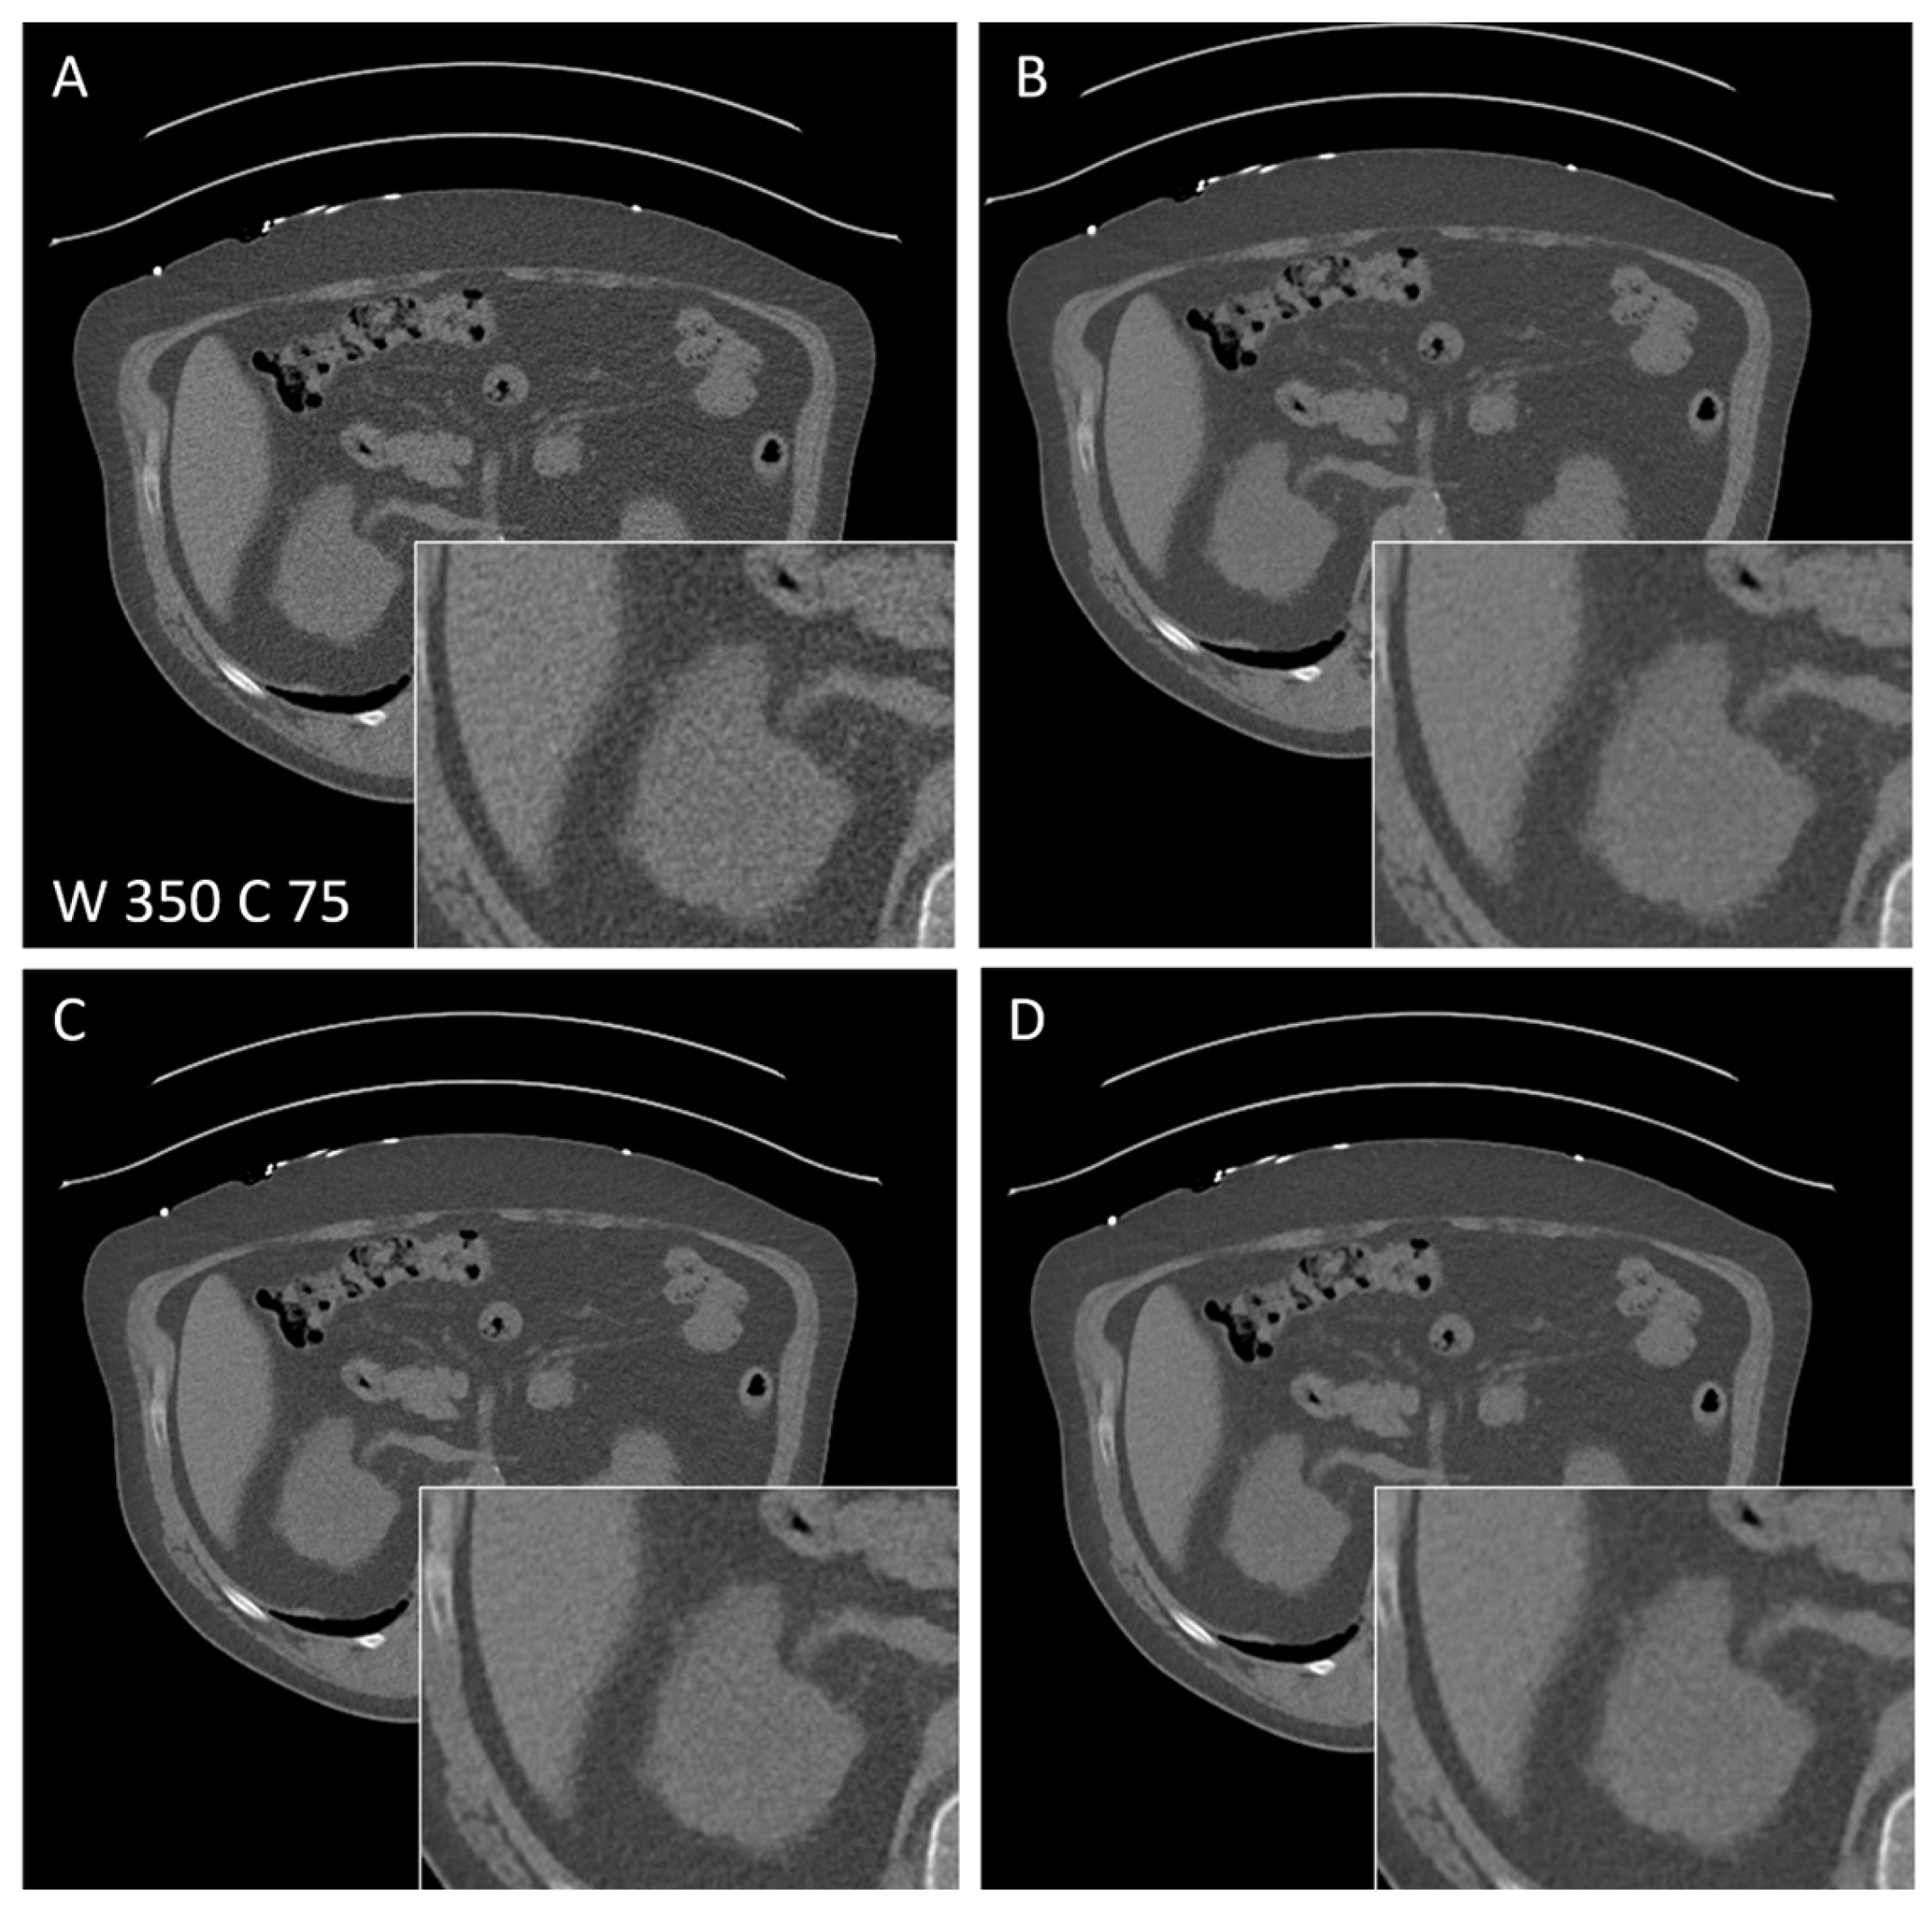

3.5. Subjective Image Quality of Abdominal CT